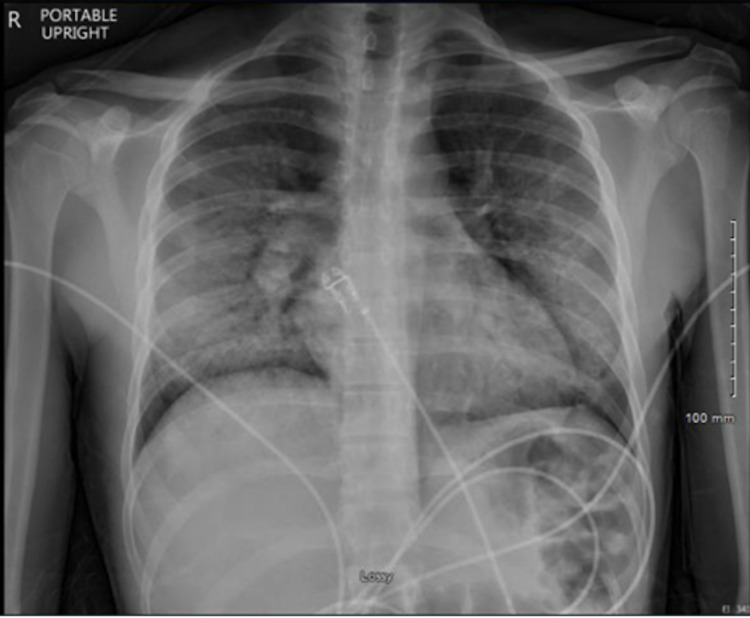

On presentation, vitals showed temperature of 100.8°F, heart rate 99, blood pressure 129/81, respiratory rate 40, SpO2 85% on room air which improved to >90% on 4L nasal cannula. The patient was not in respiratory distress and a physical exam showed crackles over right lung fields and left lingula with expiratory wheezes in the same distribution. Labs were significant for leukocytosis (18×10^3/uL) with eosinophilia (7%). CXR demonstrated diffuse bilateral airspace and interstitial opacity concerning for infection or inflammatory process including COVID-19 (Figure 1). Azithromycin was continued and ceftriaxone was initiated for possible community-acquired pneumonia (CAP).